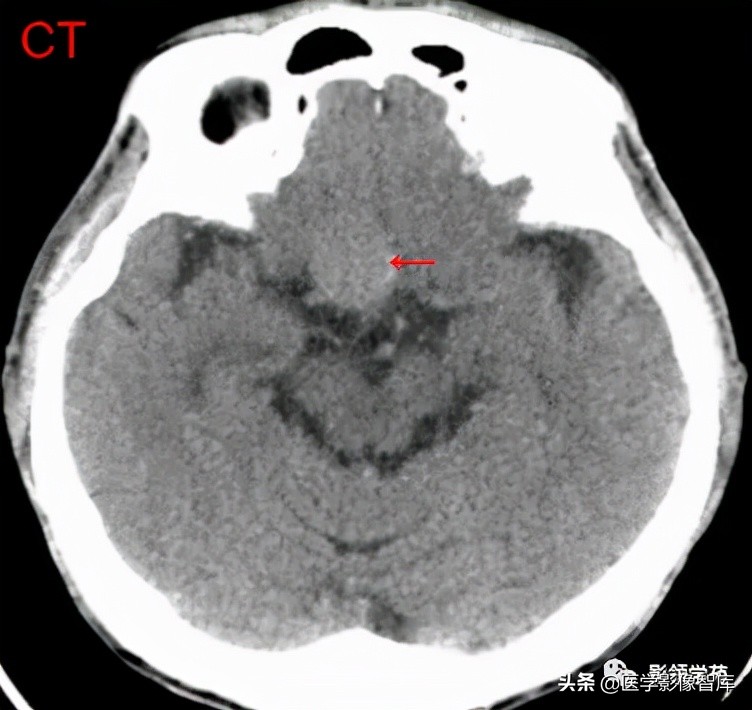

女 58岁,头晕、呕吐,桥脑右前方见一类圆形

高低混合(有血栓)T1及T2信号影,边界清楚、锐利。

明显不均匀强化(瘤内有血栓)。与基底动脉分界不清

头颅CTA:基底动脉起始部血管局部瘤样突起(宽基底),无占位效应。